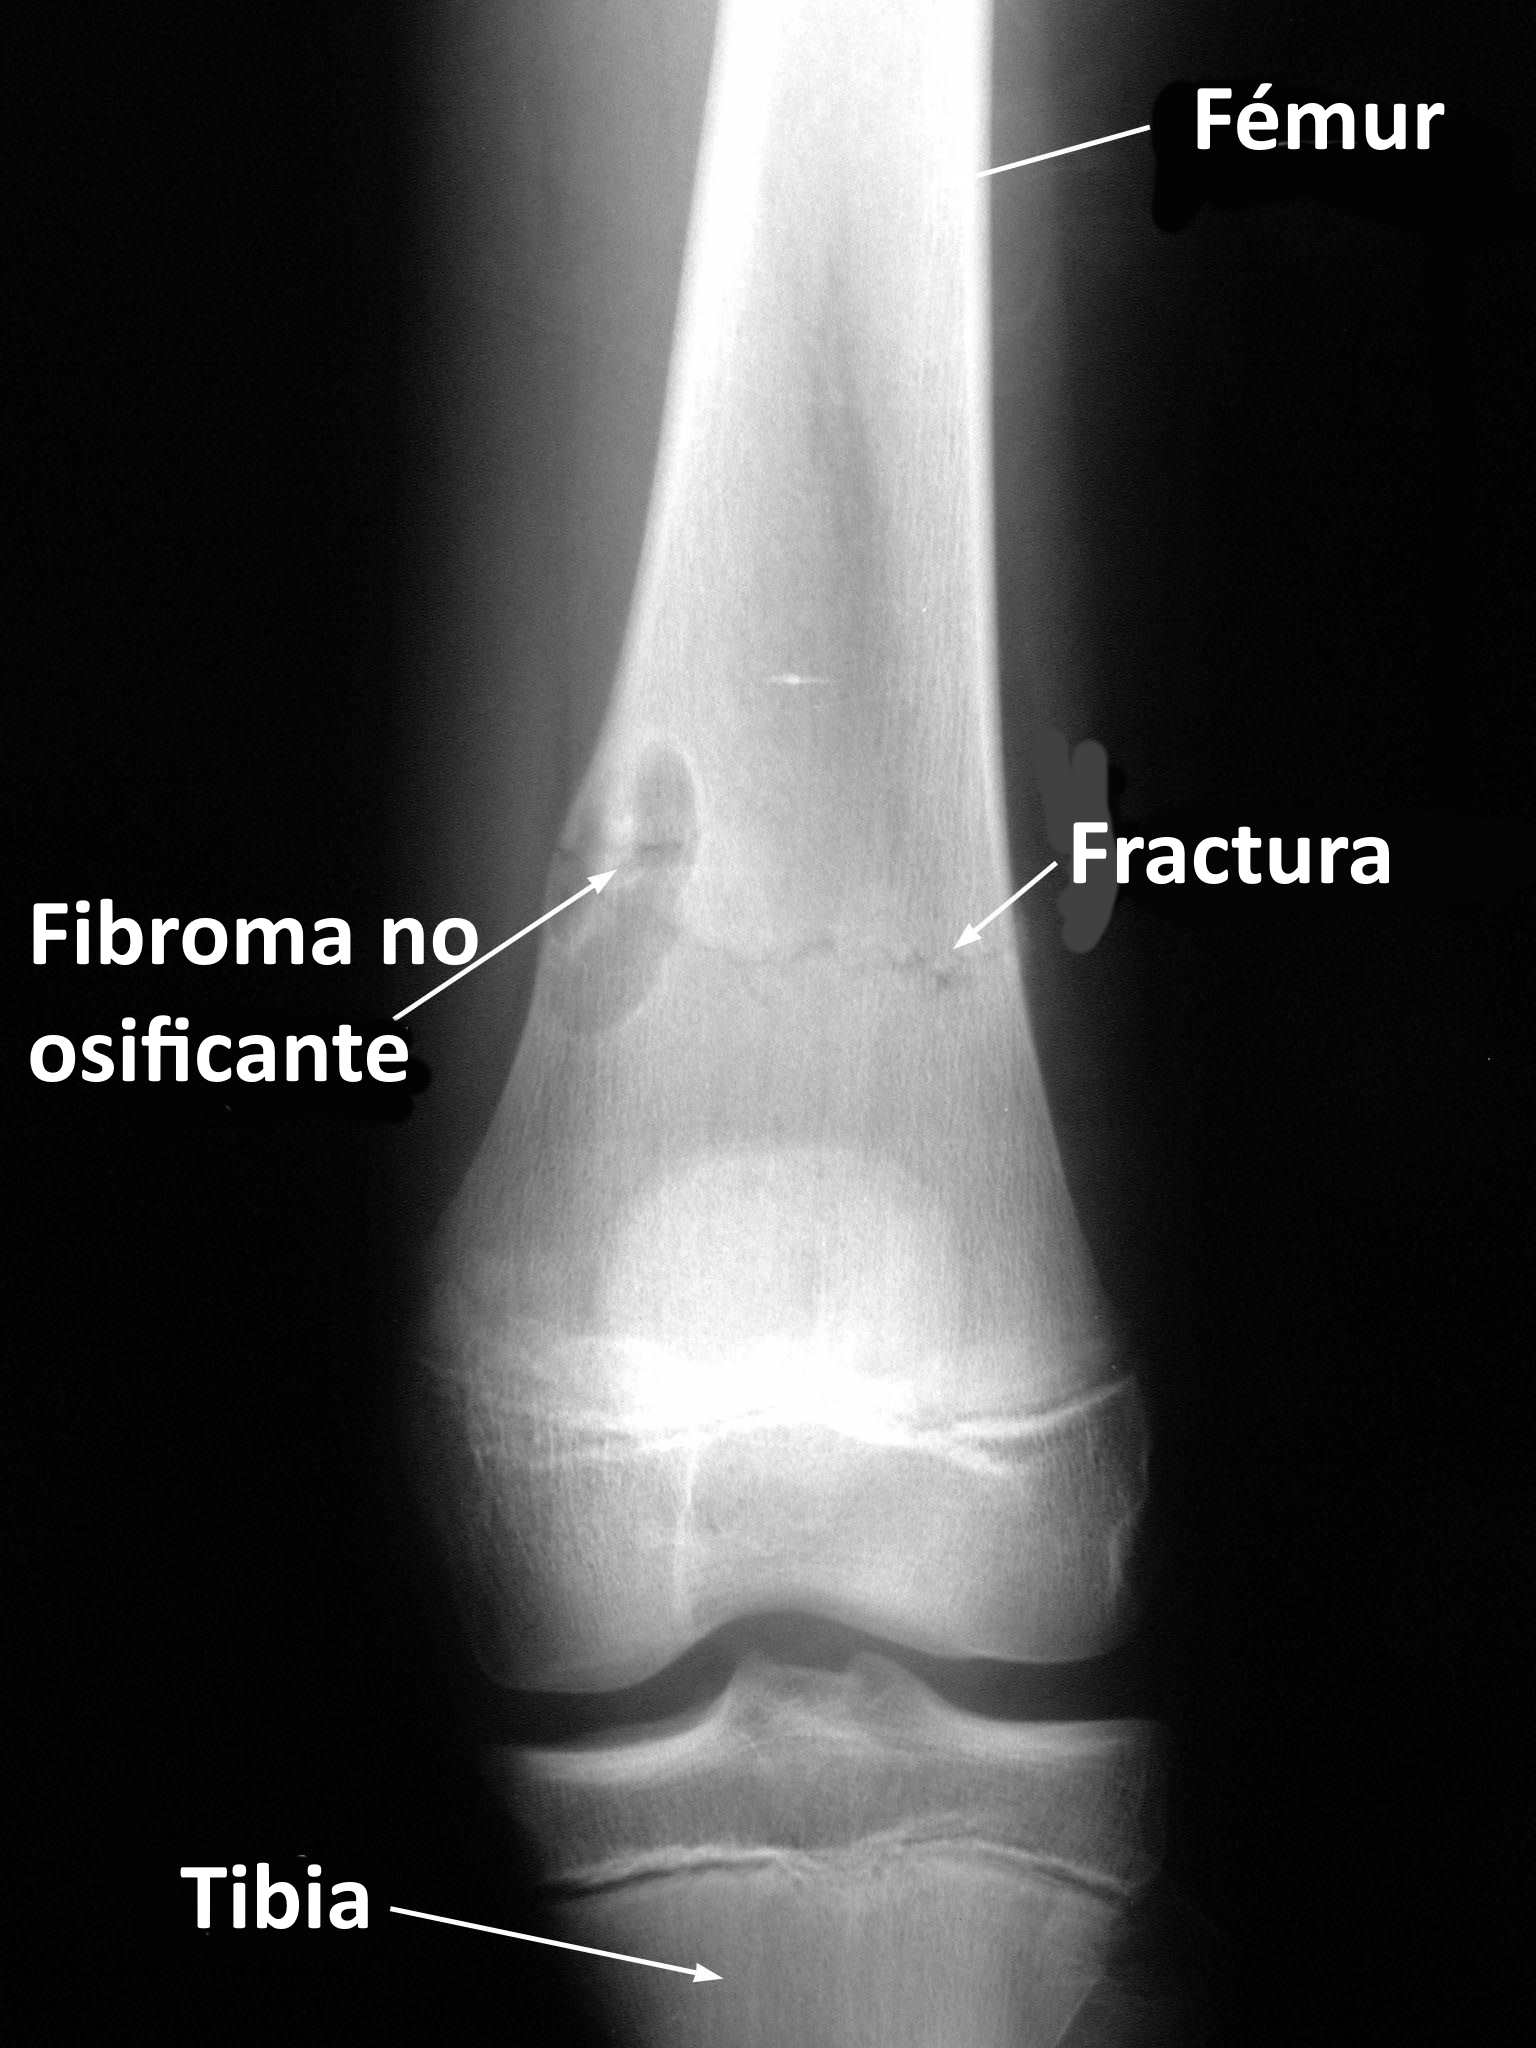

Metáfisis de huesos largos, sobre todo fémur distal y tibia (cerca de rodilla).

Lesión lítica excéntrica con margen esclerótico bien definido.

| Localización | Fémur distal, tibia proximal; también peroné | Metáfisis, excéntrico, cortical |

Radiografía simple

Suele ser suficiente. Hallazgos típicos: lesión lítica excéntrica, metafisaria, borde esclerótico bien definido, sin reacción perióstica (salvo fractura).